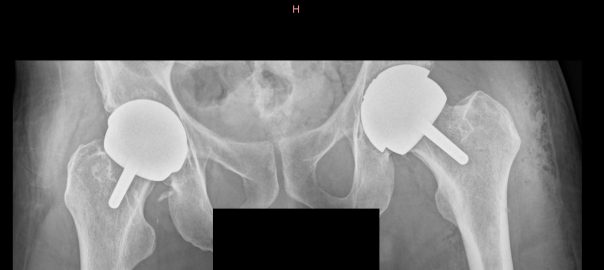

I managed to complete my Spanish homework and send it off for marking, and also got my X rays sent through from the hospital. You can see one in the banner image at the top of this blog. The implant in my left hip (on the right in the image) is the new one; the one on the left in the image was done six years ago.